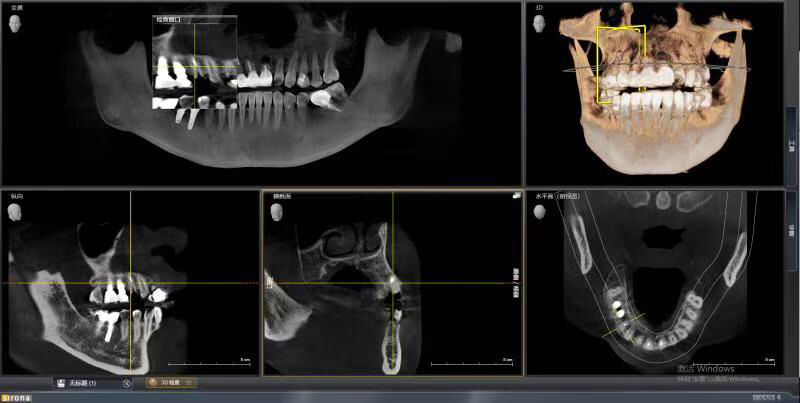

患者女,右上4号牙根管治疗后桩核冠修复,因进食硬物导致桩核冠脱落,未及时处理,导致残根无法修复,从CT上看,牙槽骨高度尚可,所以选择了即拔即种的治疗方案,且术中植骨盖膜、上愈合基台,为患者节省了就诊次数,提前了戴牙时间。